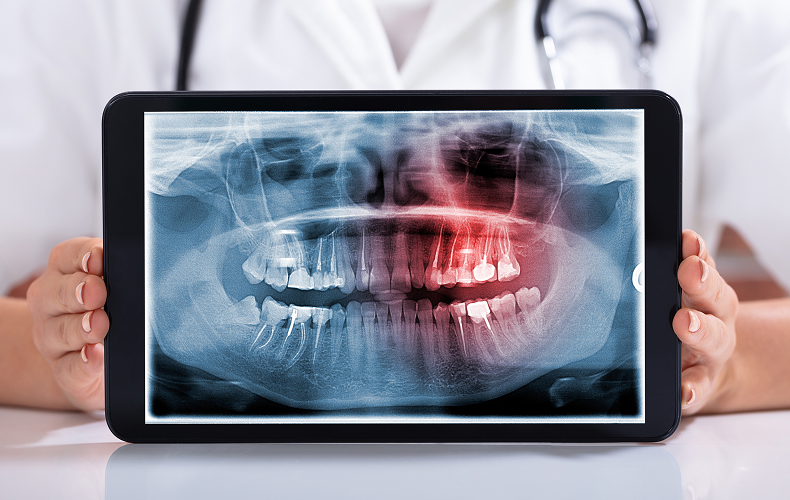

Hidden Decay

Cavities developing between teeth or under existing fillings.

Bone Loss

The early stages of gum (periodontal) disease that cause bone deterioration.

Impacted Teeth

Teeth that are trapped beneath the gums, such as wisdom teeth.

Abscesses & Cysts

Infections at the tooth’s root or other abnormalities within the jawbone.